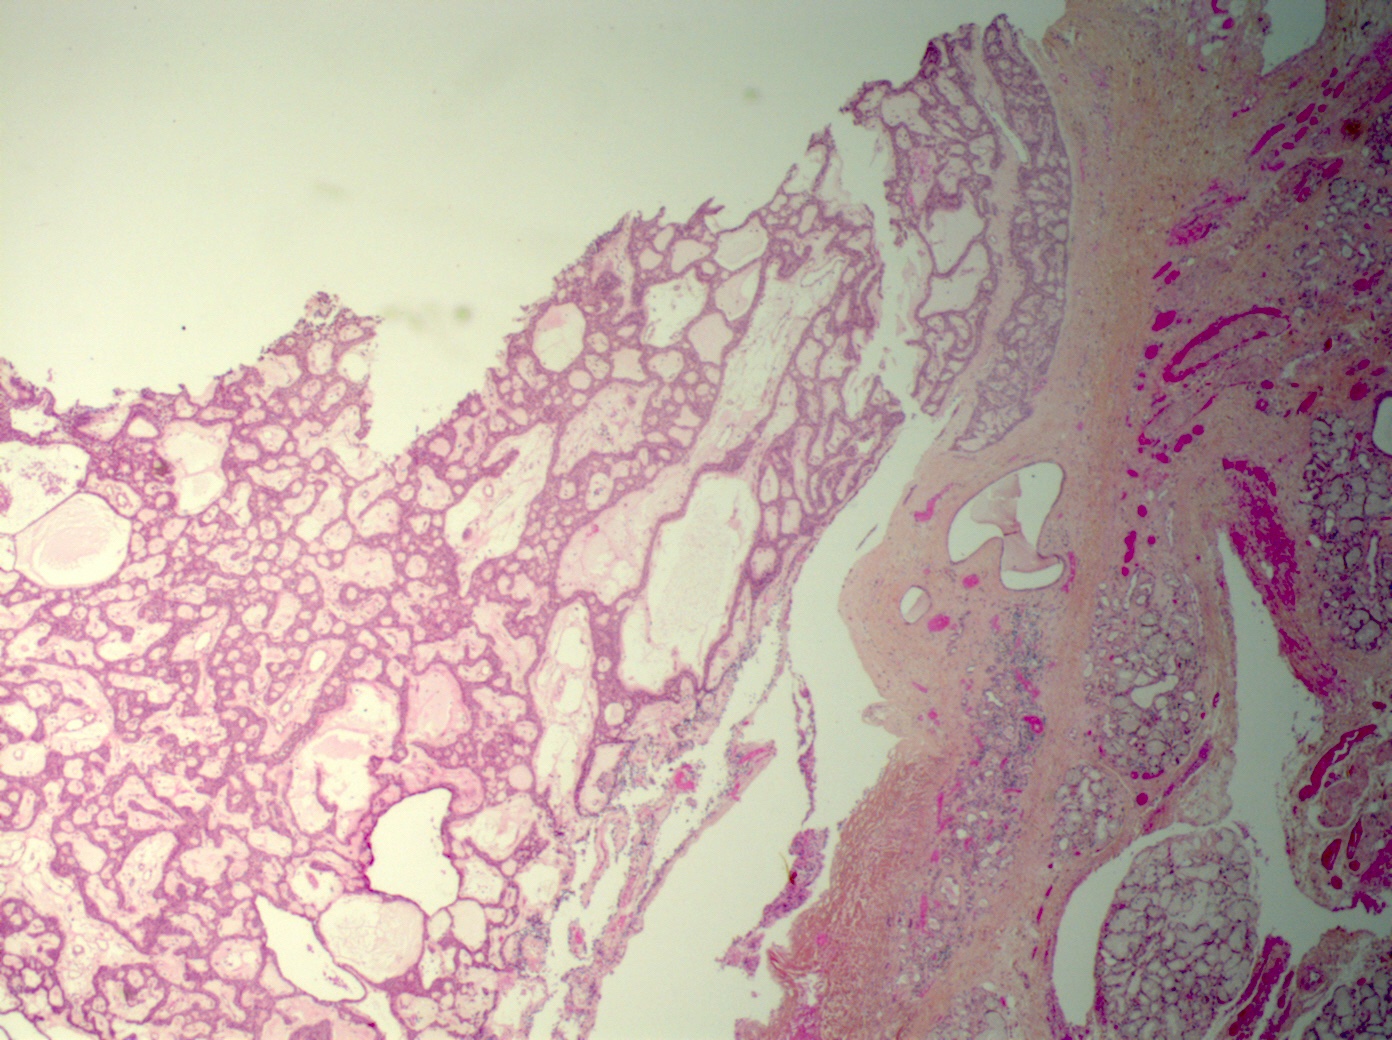

Microscopic (histologic) description

- Tumors may be single or multifocal

- Bilayered strands or ribbons or anastomosing cords or branching tubules

- Canalicular to cystic spaces between the cell strands; trabecular features

- Lack of an outer layer of myoepithelial cells

- May infiltrate capsule and show extracapsular tumor islands (including in the normal salivary gland / multiple tumors)

- Often cystic change

- Well vascularized, loose stroma; possibly sclerotic; perivascular eosinophil cuffs

- Luminal or stromal histiocytes (foamy, lipofuscin, hemosiderin), luminal hemorrhage, degenerated / infarcted stroma (Head Neck Pathol 2015;9:181)

Microscopic (histologic) images